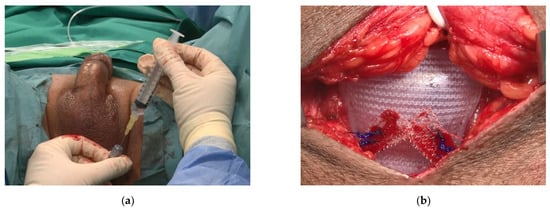

Additionally, ultrasound images performed after ATOMS adjustment at different times for serial postoperative filling in a case needing progressive filling up to 25 mL show that ATOMS filling elongates the transversal urethral diameter whereas it reduces the antero-posterior diameter (Figure 5).

Figure 5. Sonographic perineal evaluation with lineal probe shows urethral diameter (antero-posterior) diminishes with the increase in ATOMS filling volume.